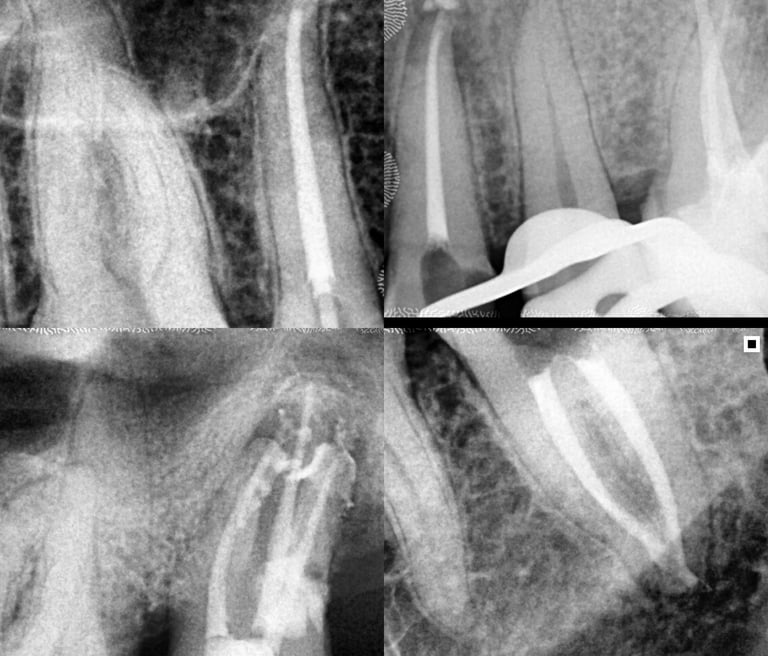

Em alguns casos, a necessidade de tratamento de canal é identificada em exames radiográficos, mesmo antes de o paciente sentir dor.

As radiografias periódicas podem revelar lesões na ponta da raiz, indicando um foco de infecção que precisa ser tratado.

Nesses casos, apenas o tratamento endodôntico é capaz de eliminar o problema e restaurar a saúde do dente.

Galeria

Na odontologia, cada sorriso é único e o resultado final depende de fatores biológicos individuais. Imagens clínicas não constituem promessa de resultado. Planejamento técnico e diagnóstico são fundamentais para o sucesso do tratamento."